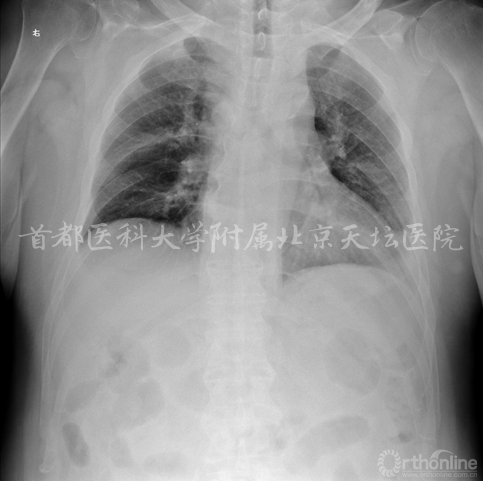

既往史:脑梗死11年,右侧肢体力弱。肺间质纤维化10年。高血压病、糖尿病、高脂血症。

相关检查:

• 肺间质纤维化 肺部感染 胸腔积液